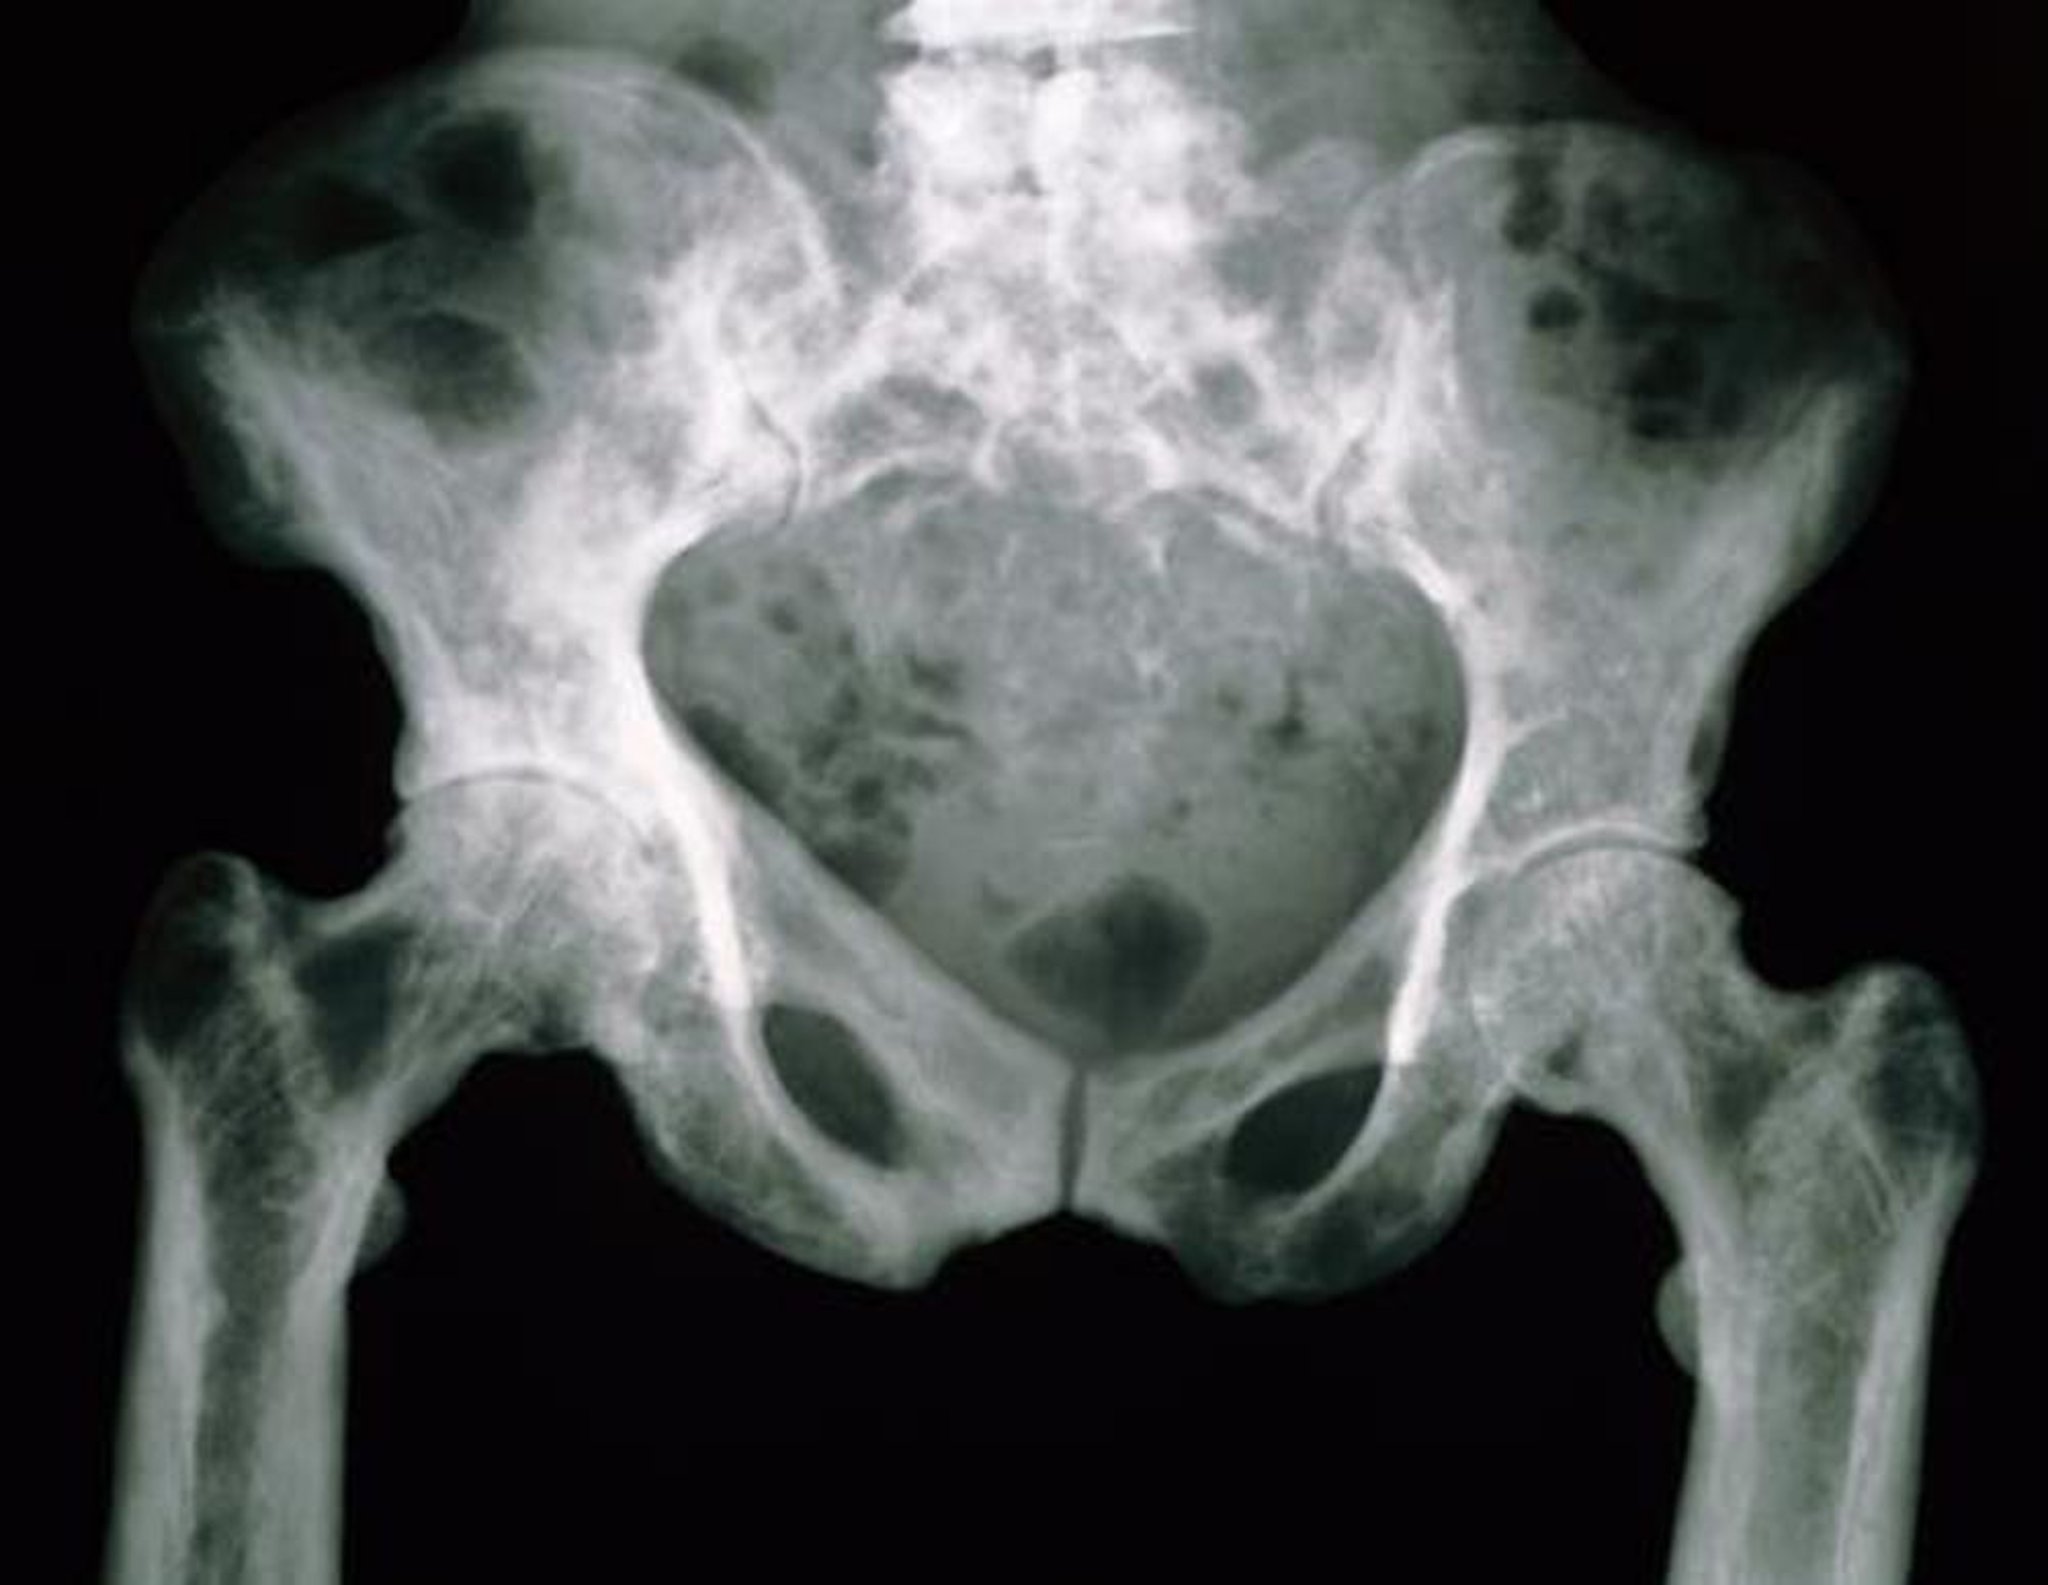

Radiografia da pelve na doença de Paget

Os ossos pélvicos nessa radiografia têm uma aparência manchada por causa da porosidade aumentada.